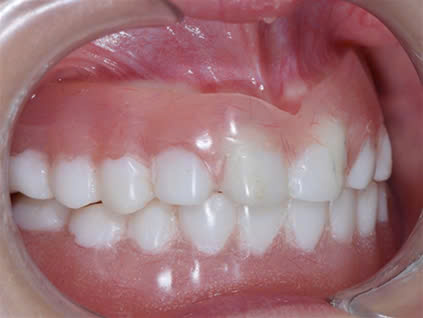

Kết hợp giữa chỉnh nha và phục hình implant: để sắp đều răng và phục hình các răng thiếu trên cung hàm.

Nhờ hàm giả mới này, khuôn mặt của trẻ thay đổi về ăn nhai cũng như mặt thẫm mỹ.

Đối với điều trị răng cho các bé từ giai đoạn ban đầu hàm giả tháo lắp giúp phục hồi chức năng ăn nhai cũng như phát âm, giao tiếp cho trẻ 1 cách tốt nhất.